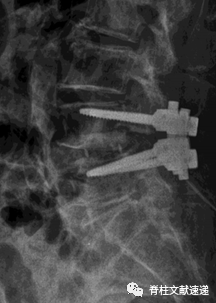

图注:根据该文献cage定位标准,该患者cage为相对靠前放置